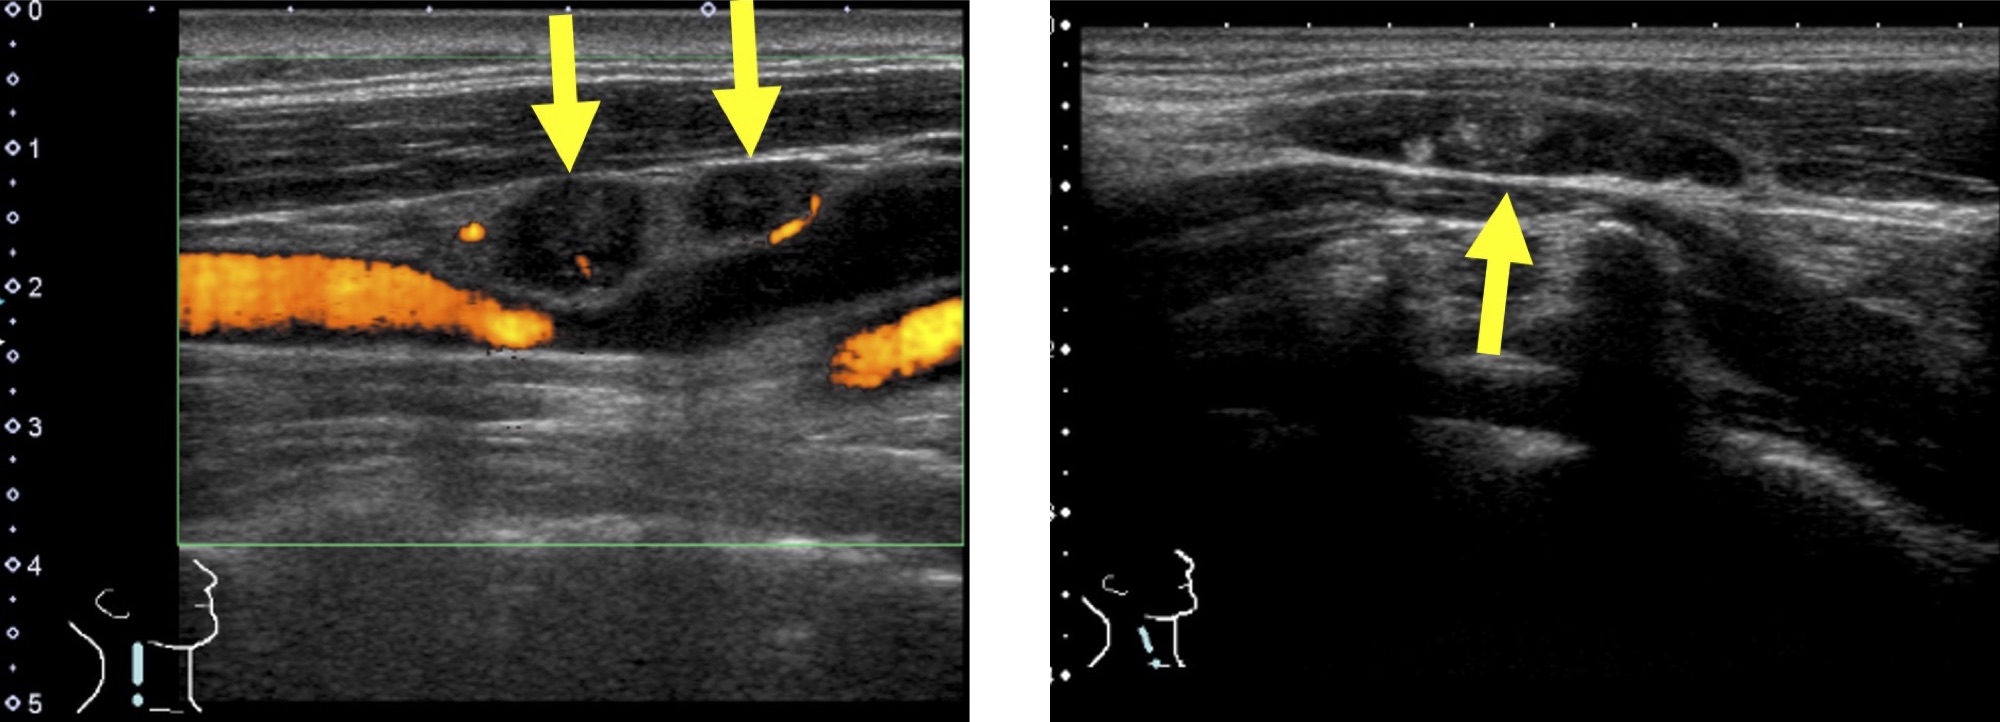

慢性甲状腺炎(橋本病)

慢性甲状腺炎(橋本病)甲状腺の表面がデコボコしています。

甲状腺全体が腫れて大きくなります。

甲状腺の内部が黒っぽくなり(エコーレベル低下)、むらがあります(内部不均質)。

※軽症の場合は正常な甲状腺とほとんど変わらない場合もあります。

亜急性甲状腺炎

痛みのある部位が黒く見えます(低エコー域)。